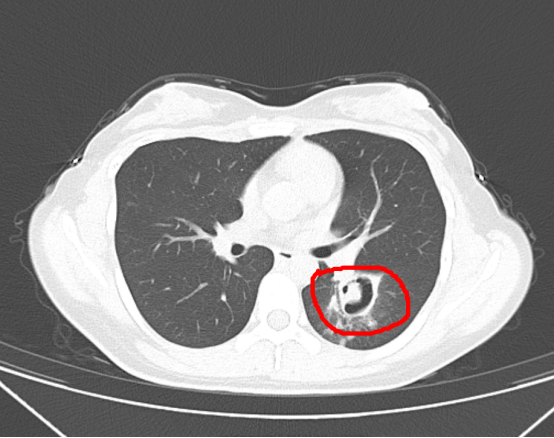

近日,王女士出現(xiàn)咳嗽、發(fā)熱等癥狀,本以為是普通感冒,沒想連續(xù)高燒三天都不見好轉(zhuǎn),只能到醫(yī)院就診。經(jīng)檢查,醫(yī)生發(fā)現(xiàn)王女士的肺部長出了一個個“小樹芽”,懷疑是霉菌性肺炎。

杭州師范大學(xué)附屬醫(yī)院感染性疾病科主任醫(yī)師 周翔:肺部(里面)出現(xiàn)一個空洞(組織壞死),做支氣管鏡進行細菌檢測,檢測出來考慮是霉菌感染(霉菌性肺炎),后來我們就用正規(guī)的抗菌治療。前天來門診復(fù)查,我們給她再做了個CT,她這個病灶已經(jīng)明顯縮小,基本好了。